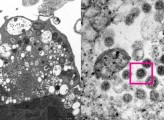

Το πανεπιστήμιο του Χονγκ Κονγκ δημοσιεύει για πρώτη φορά την εικόνα της νέας παραλλαγής Όμικρον του κοροναϊού, όπως αυτή φαίνεται μέσα από ηλεκτρονικό μικροσκόπιο.

Σύμφωνα με το APA, επιστήμονες στον τομέα της υγείας, συμπεριλαμβανομένων παθολόγων και ιολόγων, κατάφεραν να λάβουν μια ηλεκτρονική μικρογραφία ενός κυττάρου (Vero E6) από το νεφρό ενός πιθήκου που μολύνθηκε με το συγκεκριμένο στέλεχος.

Στη συνέχεια το Πανεπιστήμιο δημοσίευσε τις εικόνες χαμηλής και υψηλής μεγέθυνσης.

Στην φωτογραφία αριστερά, είναι η ηλεκτρονική μικρογραφία χαμηλής μεγέθυνσης κυττάρου νεφρού πιθήκου (Vero E6) μετά από μόλυνση με την παραλλαγή Omicron SARS-CoV-2. Δείχνει κυτταρική βλάβη με διογκωμένα κυστίδια που περιέχουν μικρά μαύρα ιικά σωματίδια.

Δεξιά, είναι η ηλεκτρονική μικρογραφία υψηλής μεγέθυνσης μολυσμένου κυττάρου Vero E6. Δείχνει συγκεντρώσεις ιικών σωματιδίων με αιχμές σχήματος κορώνας στην επιφάνειά τους (κόκκινο πλαίσιο).

Photo credit: Professor John Nicholls, Clinical Professor of Department of Pathology; and Professor Malik Peiris, Tam Wah-Ching Professor in Medical Science and Chair Professor of Virology, School of Public Health, HKUMed; and Electron Microscope Unit, HKU.